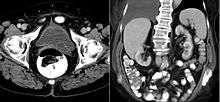

A ureterocele is a congenital abnormality found in the ureter. In this condition the distal ureter balloons at its opening into the bladder, forming a sac-like pouch. It is most often associated with a duplicated collection system, where two ureters drain their respective kidney instead of one. Simple ureterocele, where the condition involves only a single ureter, represents only twenty percent of cases. Ureterocele affects one in 4,000 individuals, at least four-fifths of whom are female. Patients are frequently Caucasian.

Since the advent of the ultrasound, most ureteroceles are diagnosed prenatally. The pediatric and adult conditions are often found incidentally, i.e. through diagnostic imaging performed for unrelated reasons.